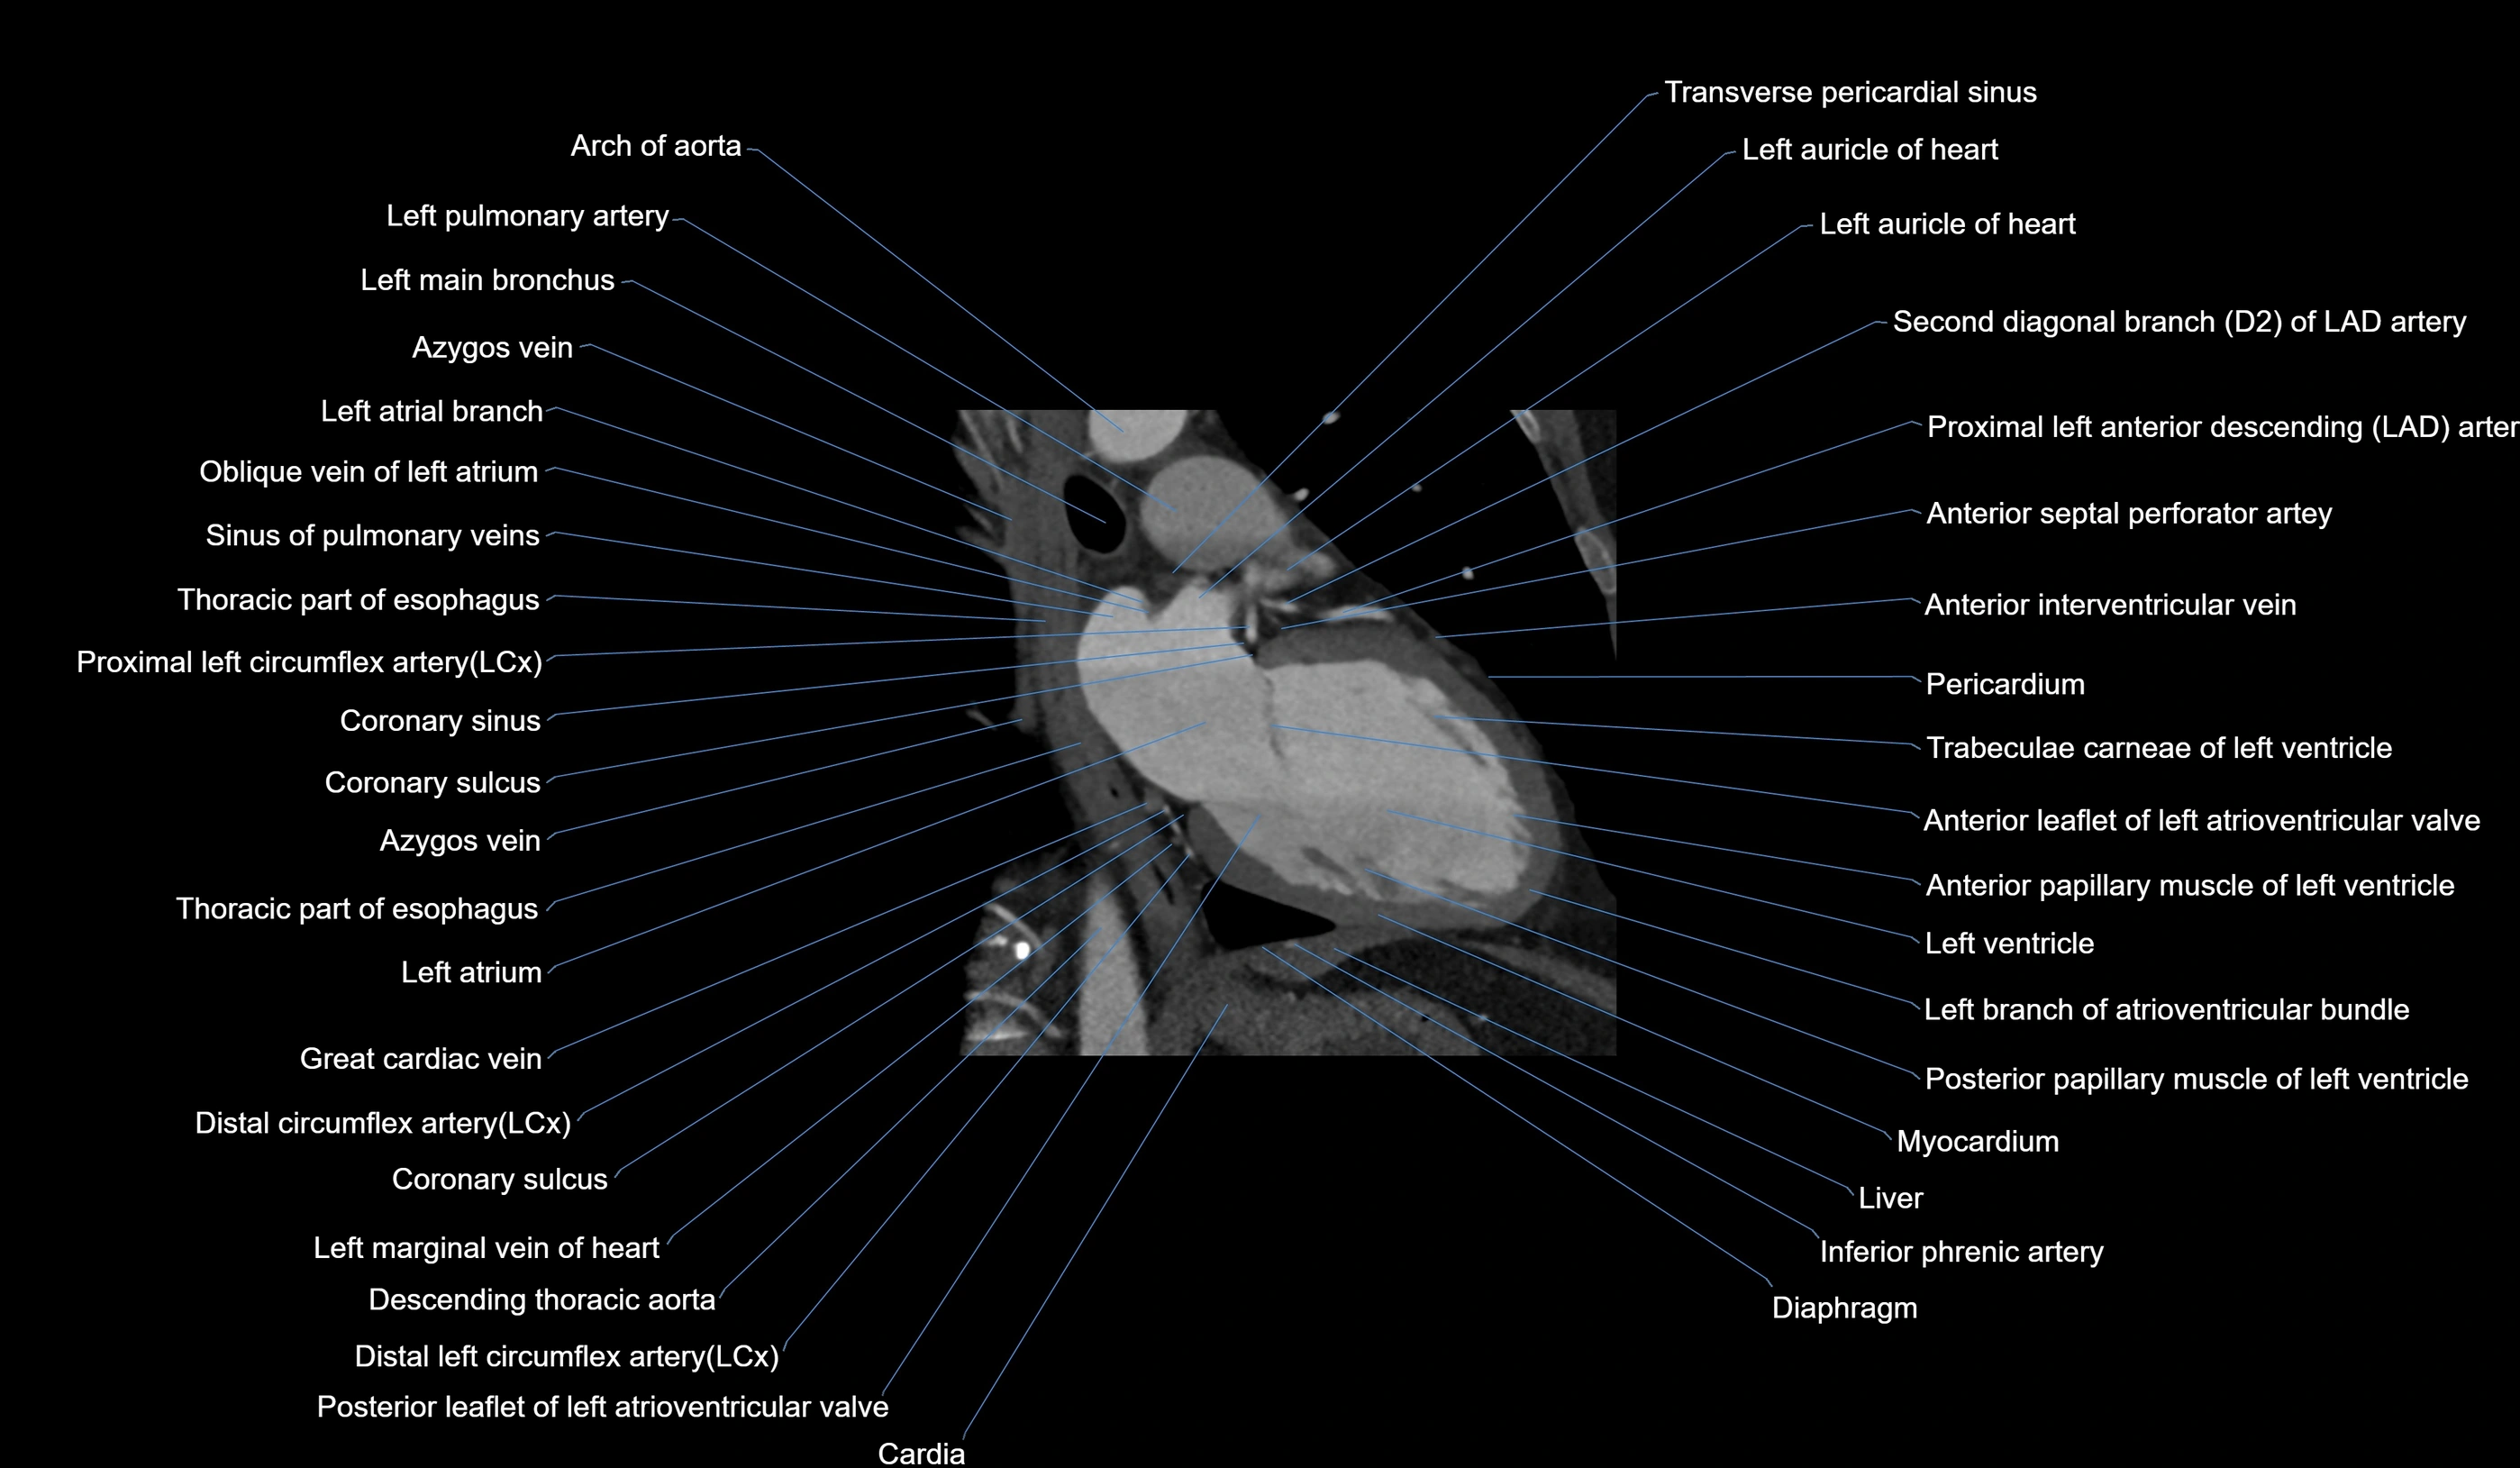

- Arch of aorta

- Left atrial branch (coronary artery)

- Left atrioventricular valve (mitral or bicuspid valve)

- Left atrium

- Left auricle

- Left branch of atrioventricular bundle

- Left main bronchus

- Left main coronary artery (LMCA)

- Left pulmonary artery

- Left ventricle

- Middle cardiac vein

- Oblique vein of left atrium

- Coronary sinus

- Coronary sulcus

- Great cardiac vein

- Circumflex artery (LCx)

- Descending thoracic aorta

- Diaphragm

- First diagonal branch (D1) of LAD

- First obtuse marginal branch

- Inferior phrenic artery

- Left anterior descending artery (LAD)

- Left marginal vein

- Posterior leaflet of left atrioventricular valve

- Second diagonal branch (D2) of LAD